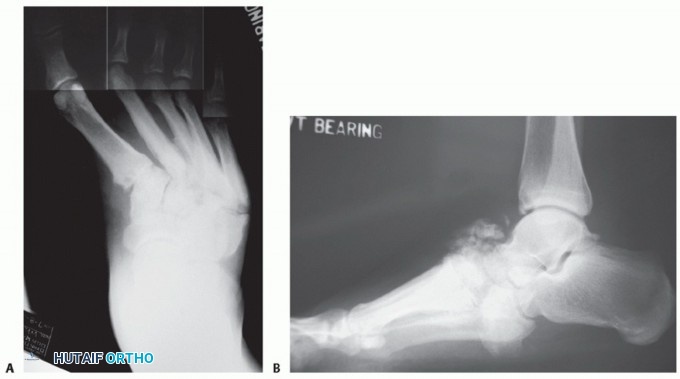

When followed longitudinally, patients who are clinically nonplantigrade, that is, have a noncolinear lateral talarfirst metatarsal axis, as determined from weight-bearing dorsal-plantar radiographs, are likely to develop

foot ulcers overlying the deformity over time.2,16 These patients are best treated with surgical correction of their acquired deformity(FIG 4).

FIG 4 • A. This 58-year-old, morbidly obese diabetic accountant is clinically bearing weight on the medial skin overlying the uncovered talar head. B. The talar-first metatarsal axis is noncolinear. Patients who are both radiographically and clinically nonplantigrade are likely to develop skin breakdown through nonplantar skin overlying bony deformity. C,D. The patient was successfully treated with surgical correction of the deformity and longitudinal management with therapeutic footwear. E,F. Clinical photographs and weight-bearing radiographs 2 years following surgery.